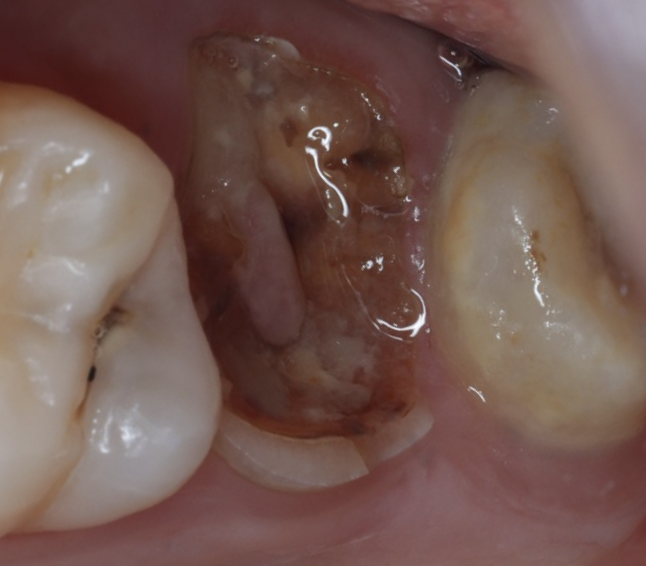

移植のリスクとして重要なのが、長期的に起こり得る歯根吸収とアンキローシス(癒着)です。

- 歯根吸収:歯の根が徐々に吸収され、歯の寿命に影響する

- アンキローシス:歯根膜が失われ、歯が骨と直接くっつく状態(動きがなくなり、咬合や将来の補綴計画に影響)

これらは、移植が「自分の歯を入れ替えるだけ」の簡単な治療ではなく、歯根膜を守る外科手技であることを意味します。